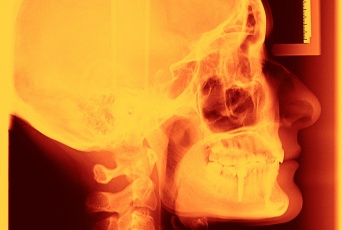

「記憶力を15%強化する新しいタイプの脳に埋め込むインプラントが開発される(米研究)」のページです。デイリーニュースオンラインは、海外などの最新ニュースを毎日配信しています。